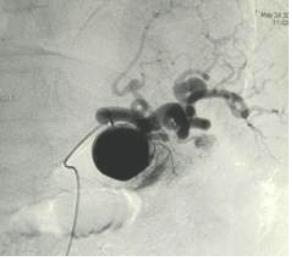

肺动静脉畸形

肺动静脉畸形分为单发、多发和弥漫性 |

这一例为多发性肺动静脉畸形 |

显示巨大静脉池显影 |

回流至肺静脉 |

肺动静脉畸形

选择其中一支畸形的滋养动脉 |

造影剂经静脉池回流至肺静脉 |

造影剂经静脉池回流至肺静脉 |